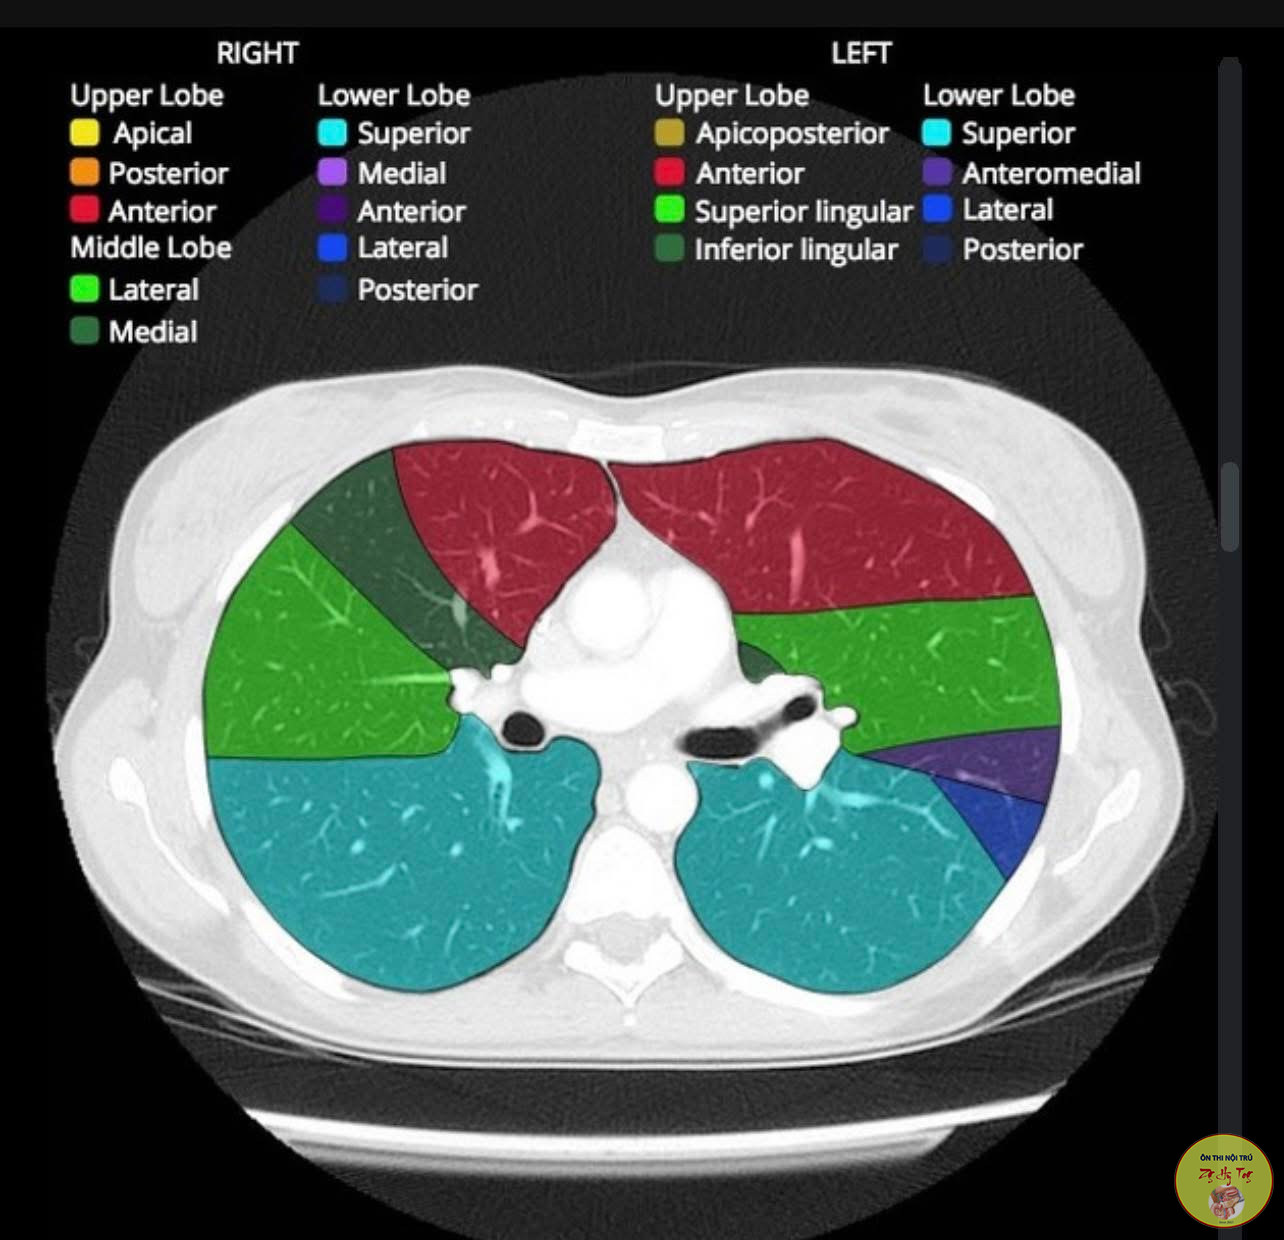

Ca lâm sàng thực tế, vận dụng lý thuyết bệnh học